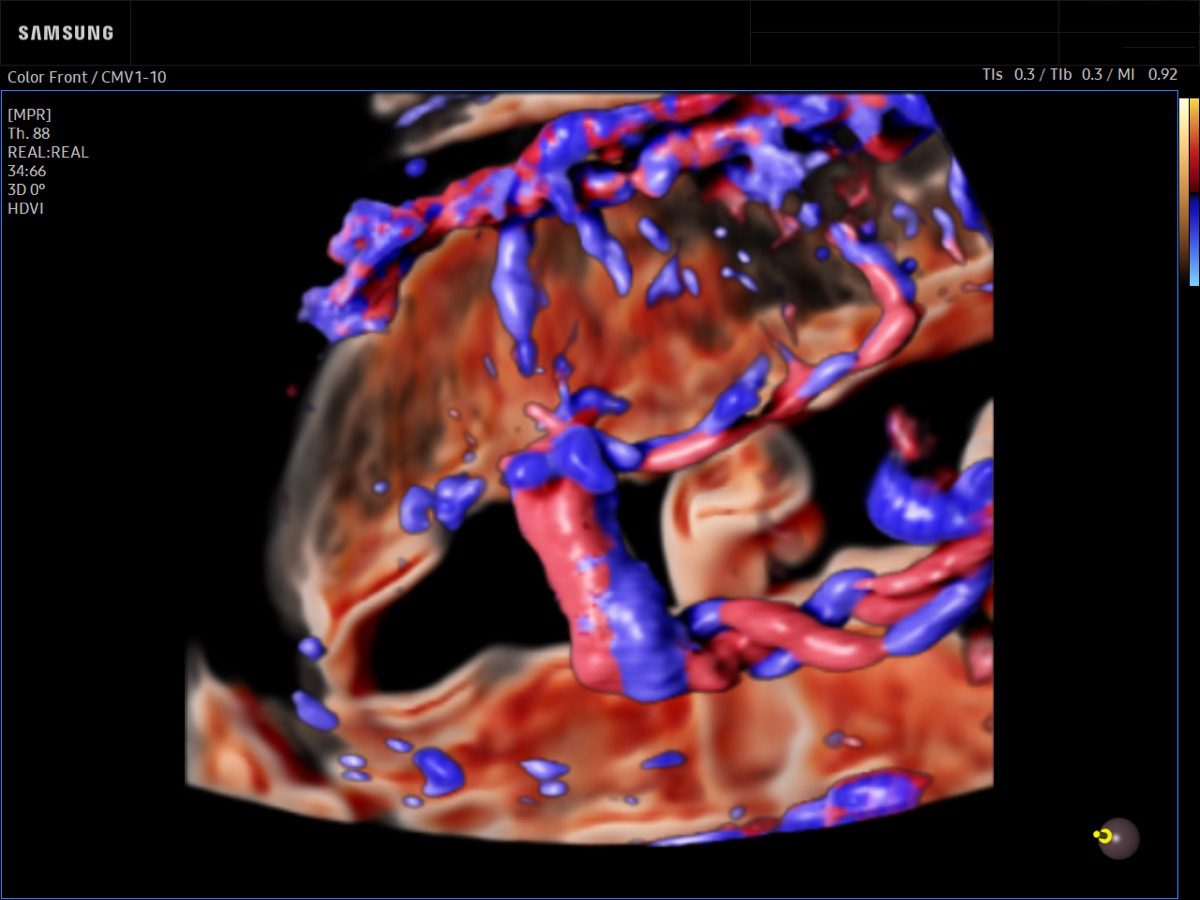

Comprehensive, advanced and expert MFM care for high-risk pregnancies

- Fetal anomalies